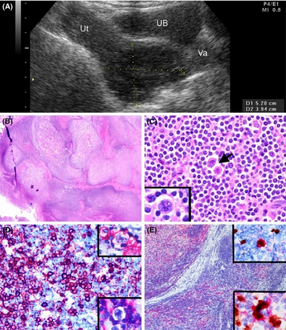

Popcorn cell in nodular lymphocyte predominant Hodgkin lymphoma - very high mag cropped.jpg

Micrograph of a lymph node biopsy showing nodular lymphocyte predominant Hodgkin lymphoma, with the Reed–Sternberg cell variant that has a popcorn-shaped nucleus (left-bottom of image). H&E stain.

NLPHL is an uncommon sub-type of Hodgkin lymphoma, making up 5-10% of Hodgkin lymphomas.[3] It is distinguished from classic Hodgkin lymphoma by the presence of CD20 positive lymphocyte predominant cells, also known as popcorn cells due to their polylobated nuclei, which look like popcorn.[3][4][5]

The characteristics of NLPHL differ from classical Hodgkin lymphoma (cHL).[9] Lymphocyte predominant (LP) ("popcorn") cells are present embedded in nodules consisting of B cells[10] and other reactive cells (mainly reactive T cells).[9] Reed-Sternberg and Hodgkin (RSH) cells are rarely seen, and immunohistochemistry shows a different pattern on the malignant cells; RSH cells typically express CD15 and CD30, whereas LP cells lack expression of these markers, but express B cell markers like CD20, CD22, and CD79a and also express the common leukocyte antigen CD45, which is uncommon on RSH cells.[9] The LP cells have scant cytoplasm and one folded or multilobated nuclei with prominent, mostly basophilic nucleoli.[10] Expert pathology review of multiple morphologic and immunophenotypic features[10] including the use of immunohistochemistry is essential.[11][12]